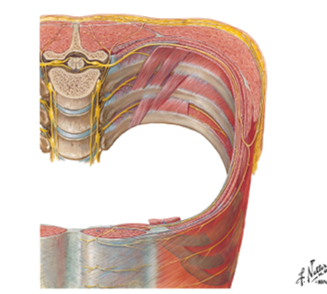

identify the actions of these muscles and their relationship to each other in space?

- External intercostals (E)

- Internal intercostals (I)

- Innermost intercostals (IM)

External intercostals (E)...inspiration...most superficial

Internal intercostals (I)...expiration

Innermost intercostals (IM)...elevate?…not completely understood...most deep

what is between the internal intercostals and the innermost intercostals? which muscle is on top?

when looking at a picture how do you identify these muscles, what should you look for?

BV's and nerves in between them

internal intercostal on top

basically, look for the innermost muscle and if its muscle colored it is the innermost intercostals...if it looks like a layer was peeled and you see nerves traveling horizontal, it indicates that you are looking at the internal intercostals

notice the external intercostal muscles

look at picture

what muscle do you see here and how do you know?

innermost intercostals because you can see the nerve and vessels driving into the muscle indicating that you can see the innermost intercostals (you are looking inside the chest so the IM are the deepest muscles inside)

_______ thoracic spinal nerves exit the spinal IVF?

what supplies the intercostal spaces? what is the spacial relationship of these things that enter the intercostal space?

12

Anterior rami supplies the intercostal spaces

“VAN” – vein, artery, nerve bundle entering the intercostal space (from top to bottom)

what are these nerves that are going horizontal?

follow how it curves around and notice how it splits and then goes to the front and back

intercostal nerves

Identify/describe the intercostal artery pathway?

- Intercostal arteries/veins run in the ___________ aspect of

the intercostal space?

- They are ________ to the “superior rib” of the intercostal space?

- Collateral branches of intercostal arteries/veins run in the _________ aspect of the intercostal space

superior aspect

inferior

inferior

describe whats in the intercostal spaces from superior to inferior?

These travel in intercostal space together just ________ to rib

- There is a second set of smaller collaterals located ________ to each rib

- Vein

- Artery

- Nerve

inferior

superior

notice in picture how the vein artery and nerve (VAN) is just below the rib and then more down in the intercostal space just above the rib are the collateral vessels

vein, artery and nerves are located just ______ each rib?